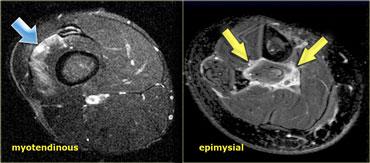

Có 2 dạng tổn thương được tìm thấy trong căng cơ.

Cho đến nay, dạng phổ biến nhất là dạng tổn thương tại chỗ nối cơ-gân, chiếm khoảng 97% trường hợp.

3% còn lại sẽ biểu hiện dạng căng cơ ngoại mạc cơ, với các bất thường được tìm thấy ở ngoại vi của cơ.

Bên trái là hình ảnh ví dụ về một vận động viên cử tạ với hình thái rách cân cơ ngoài (epimysial).

Gân bị rách tại điểm nối cơ-gân, và dịch thoát ra xung quanh bờ cơ tạo nên hình ảnh rách cân cơ ngoài.

Cơ dưới vai là cơ hội tụ (giống như cơ ngực chẳng hạn) với nhiều gân.

Phù nề sẽ có dạng phân bố đa lông chim, khi phù nề lan theo nhiều hướng dọc theo các gân khác nhau.